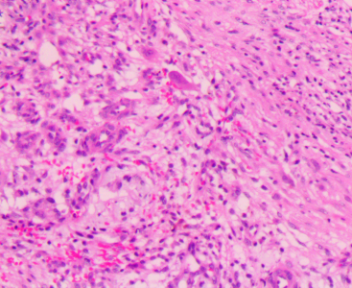

上臂肿物

标本名称

大体所见

灰白不规则软组织1块1.5x1.5x1cm。

图4